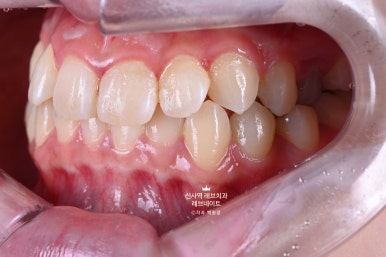

어쨌든 앞에서 보니, 확실히 다르더라구요.

아주 어려운 상황에서, 자연스러운 아름다움을 잘 찾아낸 것 같습니다.

입 안에서 보면 더 자연스럽습니다.

가로로 길어보이는 치아는 이 정도 웃어서는 보이지 않아요. ㅎㅎ

치아 사이의 공간도 넓었고, 교합도 좌우가 달라 너무너무 어려웠던 라미네이트 케이스였습니다.

'당연히' 교정적인 해결이 필요하나, 환자분의 아나운서 면접 일정이 중요해서 치료 계획을 바꿔야만 했던 케이스.

뽑을까 말까 고민했던 송곳니는 뽑지 않았고,

일단 보이는 쪽에만 최대한 단단한 강도를 갖는 라미네이트로 커버해드렸습니다.